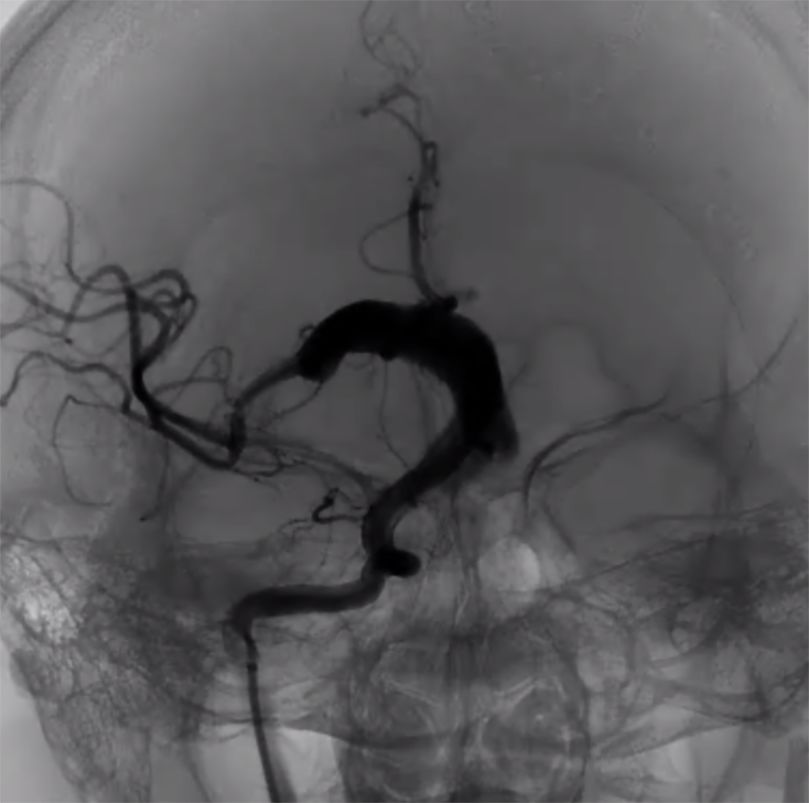

(6)造影见动脉瘤内血流通路形成(图9)。

图9

(7)支架重建后正侧位(图10)。

图10